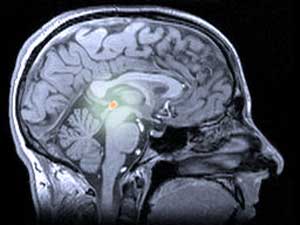

인간과 다른 동물에서 멜라토닌은 뇌 깊숙이 위치한 다소 신비로운 구조물인 송과선(‘파이-닐’로 발음)에서 생성돼요. 송과선은 일부 도마뱀의 경우 머리 꼭대기에 위치하여 날아다니는 포식자의 그림자를 감지하는 데 사용되기 때문에 때때로 ‘제3의 눈’이라고 불리기도 해요.